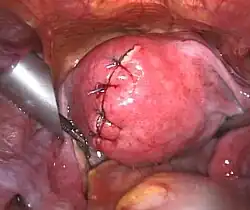

-

Uterus prior to hysterectomy

Uterus prior to hysterectomy -

Laparoscopical hysterectomy

Laparoscopical hysterectomy -

Cervical stump (white) after removal of the uterine corpus at laparoscopic supracervical hysterectomy

Cervical stump (white) after removal of the uterine corpus at laparoscopic supracervical hysterectomy -

Transvaginal extraction of the uterus in total laparoscopical hysterectomy

Transvaginal extraction of the uterus in total laparoscopical hysterectomy -

End of a laparoscopical hysterectomy

End of a laparoscopical hysterectomy